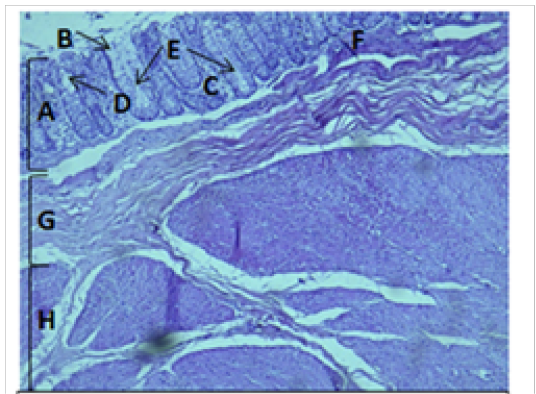

Histological section of cecum Showing:

A- Mucosa B- Epithelium C- Lamina proparia D- Goblet cell E- Crypts of lieberkuhn F- Muscularis mucosa G- Submucosa H- Muscularis Externia H&E 100X